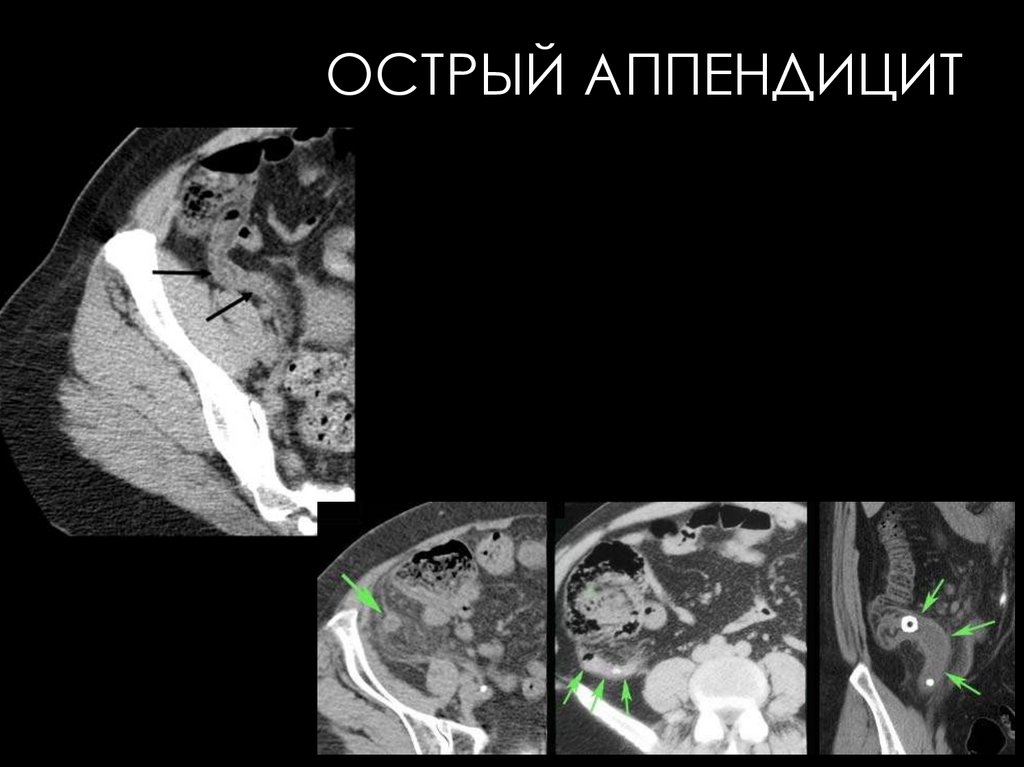

119. Острый аппендицит

ОСТРЫЙ АППЕНДИЦИТ

• При остром флегмонозном или деструктивном

аппендиците: небольшие скопления газа и жидкости

в дистальных петлях подвздошной кишки и в слепой

кишке. Стенка слепой кишки утолщена за счет отека.

При изменении положения тела кишка не смещается.

Если образуется абсцесс вокруг червеобразного

отростка, то на стенке кишки он обусловливает

вдавление.

• При термографии в случае острого аппендицита

определяется повышение температуры над правой

подвздошной областью на 2—3 °С.

• Ультразвуковое исследование позволяет обнаружить

утолщение стенок кишки и аппендикулярный

инфильтрат.

• ограниченное

вздутие

кишечных

петель

в

илеоцекальной области,

• четкий

горизонтальный

уровень жидкости в слепой

кишке,

• мелкие нечеткие уровни

жидкости в терминальном

отделе подвздошной кишки

(прободной аппендицит)